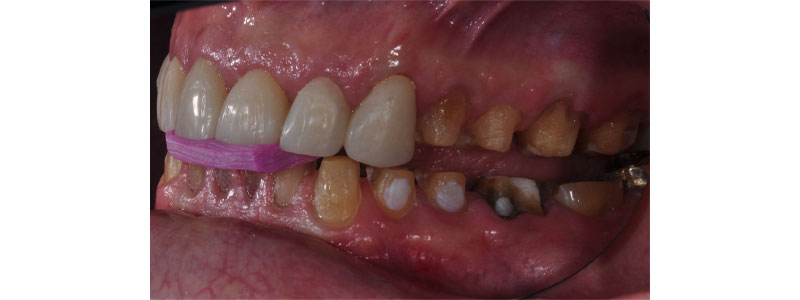

Restoring and managing anterior guidance is critical for success in rehabilitating worn dentitions. Altering the vertical dimension can be a key component in that success. The image provided references how the change in VDO affects the anterior tooth relationship. In an open bite situation, closing the vertical dimension will bring the anterior teeth closer together, creating a more ideal relationship.

Alternatively, opening a deep bite will provide increased distance between the incisors. A shallower guidance may be attained. This decreases overbite and overjet. Care must be taken when opening Class II-type situations. The downward rotation of the mandible will create a greater Class II condition that potentially increases overjet. Using facebow-mounted models will aid in visualizing the changes in anterior tooth relationships as the VDO is opened or closed.